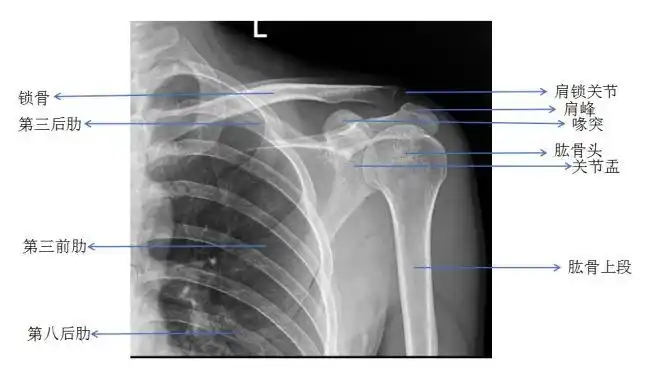

肩关节x线检查体位大全